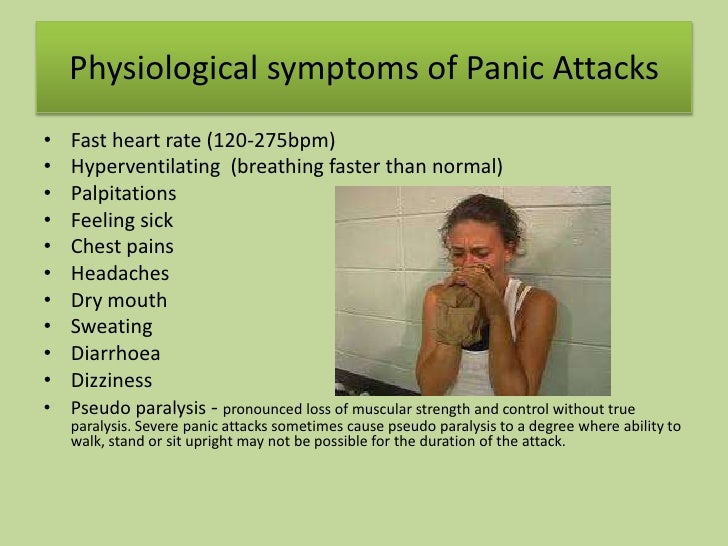

The development of treatments for COVID-19 is currently in progress however, their effects remain limited, and the development of more effective therapeutics is desired. Diagnosis and management of generalized anxiety disorder and panic disorder in adults.Since the first case of COVID-19 was reported in Wuhan, China, in December 2019, the SARS-CoV-2 epidemic has spread all over the world and has become a significant public health issue. Novel insights into pathological anxiety and anxiety-related disorders.

Medicationĭoctors may recommend the following medications for pathological anxiety: These may include self-assessment questionnaires, interviews with therapists, and various clinical scales such as the Generalised Anxiety Disorder Assessment-7 and the Severity Measure for Panic Disorder.ĭoctors typically treat anxiety problems with medication, psychotherapy, or a combination of the two. The doctor may also use specialized mental health tests to help them diagnose the individual. The doctor may then order laboratory tests such as:ĭepending on the results of these tests, a doctor may recommend further evaluations, including: They may begin with a complete physical exam and thorough medical history to help rule out any other medical disorders that could cause the individual symptoms. Because pathological anxiety can manifest in various ways and other factors, such as illness, can cause it, a doctor may use various assessments to help them diagnose the condition.